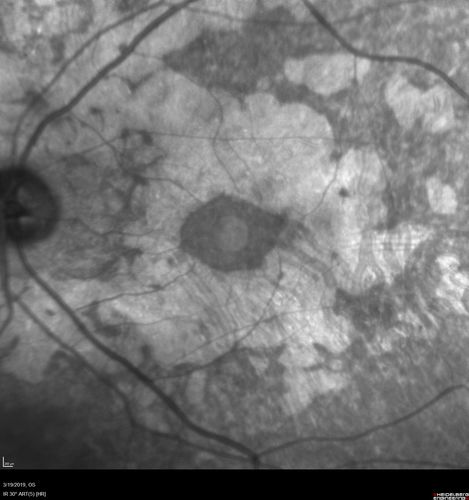

Concentric Geographic Atrophy - 76 year old man

Gradual vision loss, worse at night. VA 20/40 OU.

Concentric Geographic Atrophy - 76 YO male